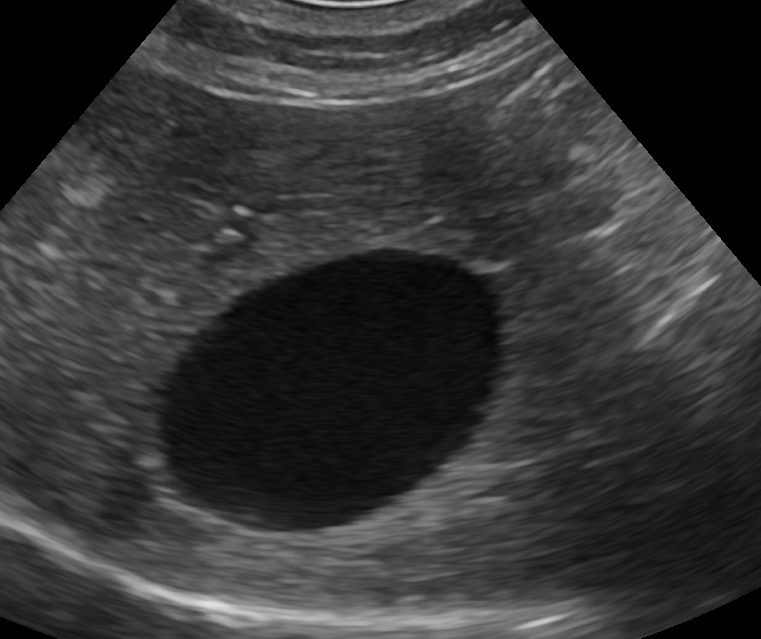

胆泥症は無症状で経過することが多いため、定期的な健康診断で早期発見を心がけましょう。 また、胆嚢炎や内分泌疾患( 甲状腺機能低下症 や 副腎皮質機能亢進症 )などのような、

犬 胆泥症 原因-胆泥 をかたちづくっているのは コレステロール や 黄疸色素 ( ビリルビン )、 カルシウム などの微細な 結晶 が 胆嚢壁 から分泌される 粘液 に包まれたものと考えられますが、他にも 炎症 によっこんにちは。獣医師の清水いと世です。 今回は、わんちゃんの胆泥症について説明します。 前編は、胆泥症の原因や検査方法や症状について、後編は治療や予防方法について説明します。 犬の胆泥

胆泥症・胆石症について 胆嚢は、胆汁を産生し貯留する器官です。 胆汁には、脂肪を分解し水に溶けやすい状態に(乳化)する役割を持っています。 胆嚢に貯えられた胆汁は、元々サラサラの水胆泥を生じさせた原因や疑われる原因があれば、それを取り除きます。 そのために、 犬の胆泥症 <前編> で説明した原因追及のための検査結果が重要になります。 肝臓の異常が認められるので